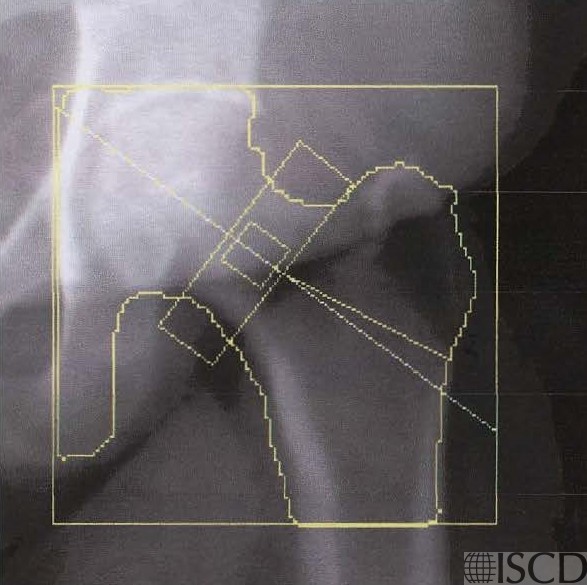

This is the follow up Hologic left hip scan 2 years later. There is a large increase at the femoral neck and no significant change a the total hip

This is patient is 61″ tall and weight 273 pounds, with BMI = 51.8. The interval change was discordant between the total hip and femoral neck after 2 years. There was not a significant change at the total hip using the facility 95% confidence interval. There is a 21% increase at the femoral neck, which was a significant increase. The position of the panniculus was different between the two scans, and the position of the panniculus is documented on the single energy images. It is important to have a standard operating procedure which recommends that the patient should retract their panniculus at each scan, making the position of the panniculus consistent.